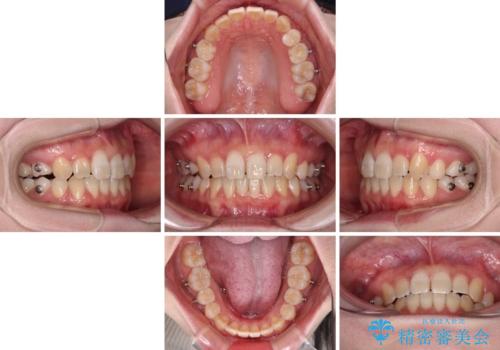

- インビザライン

- 1年7ヶ月

インビザラインを用いて、前歯の叢生を解消するとともに、ディープバイトを改善していくこととしました。